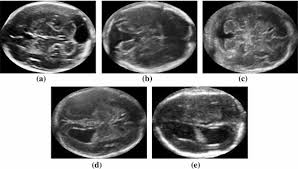

This newborn was also diagnosed with hearing loss

What is congenital CMV?